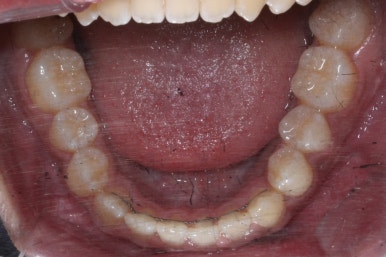

위 사진들은 부산주걱턱교정 키다리아저씨치과에 내원하셨을 당시의 입안 모습입니다.

입 안의 모습에서도 주걱턱의 특징으로는

하악이 앞으로 나와있습니다.

윗니는 뻐드러지고 아래 앞니는 뒤쪽으로 쓰러져 있습니다.

교합이 맞지 않습니다.